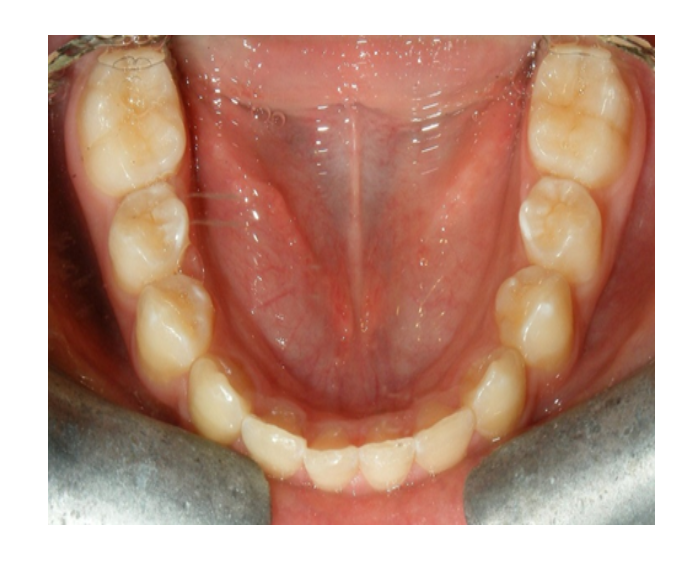

Prótesis fija de zirconia

sin metal